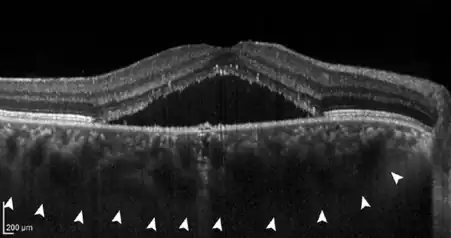

- If further damage to Bruch's membrane and the pigment epithelium causes fluid to accumulate under the retina, central serous chorioretinopathy (CCS) develops. In this stage, patients often have blurred vision and report a reduction in visual acuity with perception of a central "grey spot". In the majority of patients, spontaneous resolution of the subretinal fluid occurs within a few months, but recurs in up to 50% of cases. In some patients the fluid remains, making it a chronic disease; medical therapy or the application of various laser methods is possible.

- In about 25% of all patients with a chronic central serous chorioretinopathy, a proliferation of blood vessels from the choroid towards the retina can be detected (choroidal neovascularisation, CNV). CNV forms after an average of 17 years.[4] This stage is called pachychoroid neovasculopathy (PNV), [4] which can cause a massive reduction in vision due to bleeding and scarring of the macula.[5] Anti-VEGF therapy, which is injected directly into the eye (intravitreally), has proven to be an effective therapy in this case.